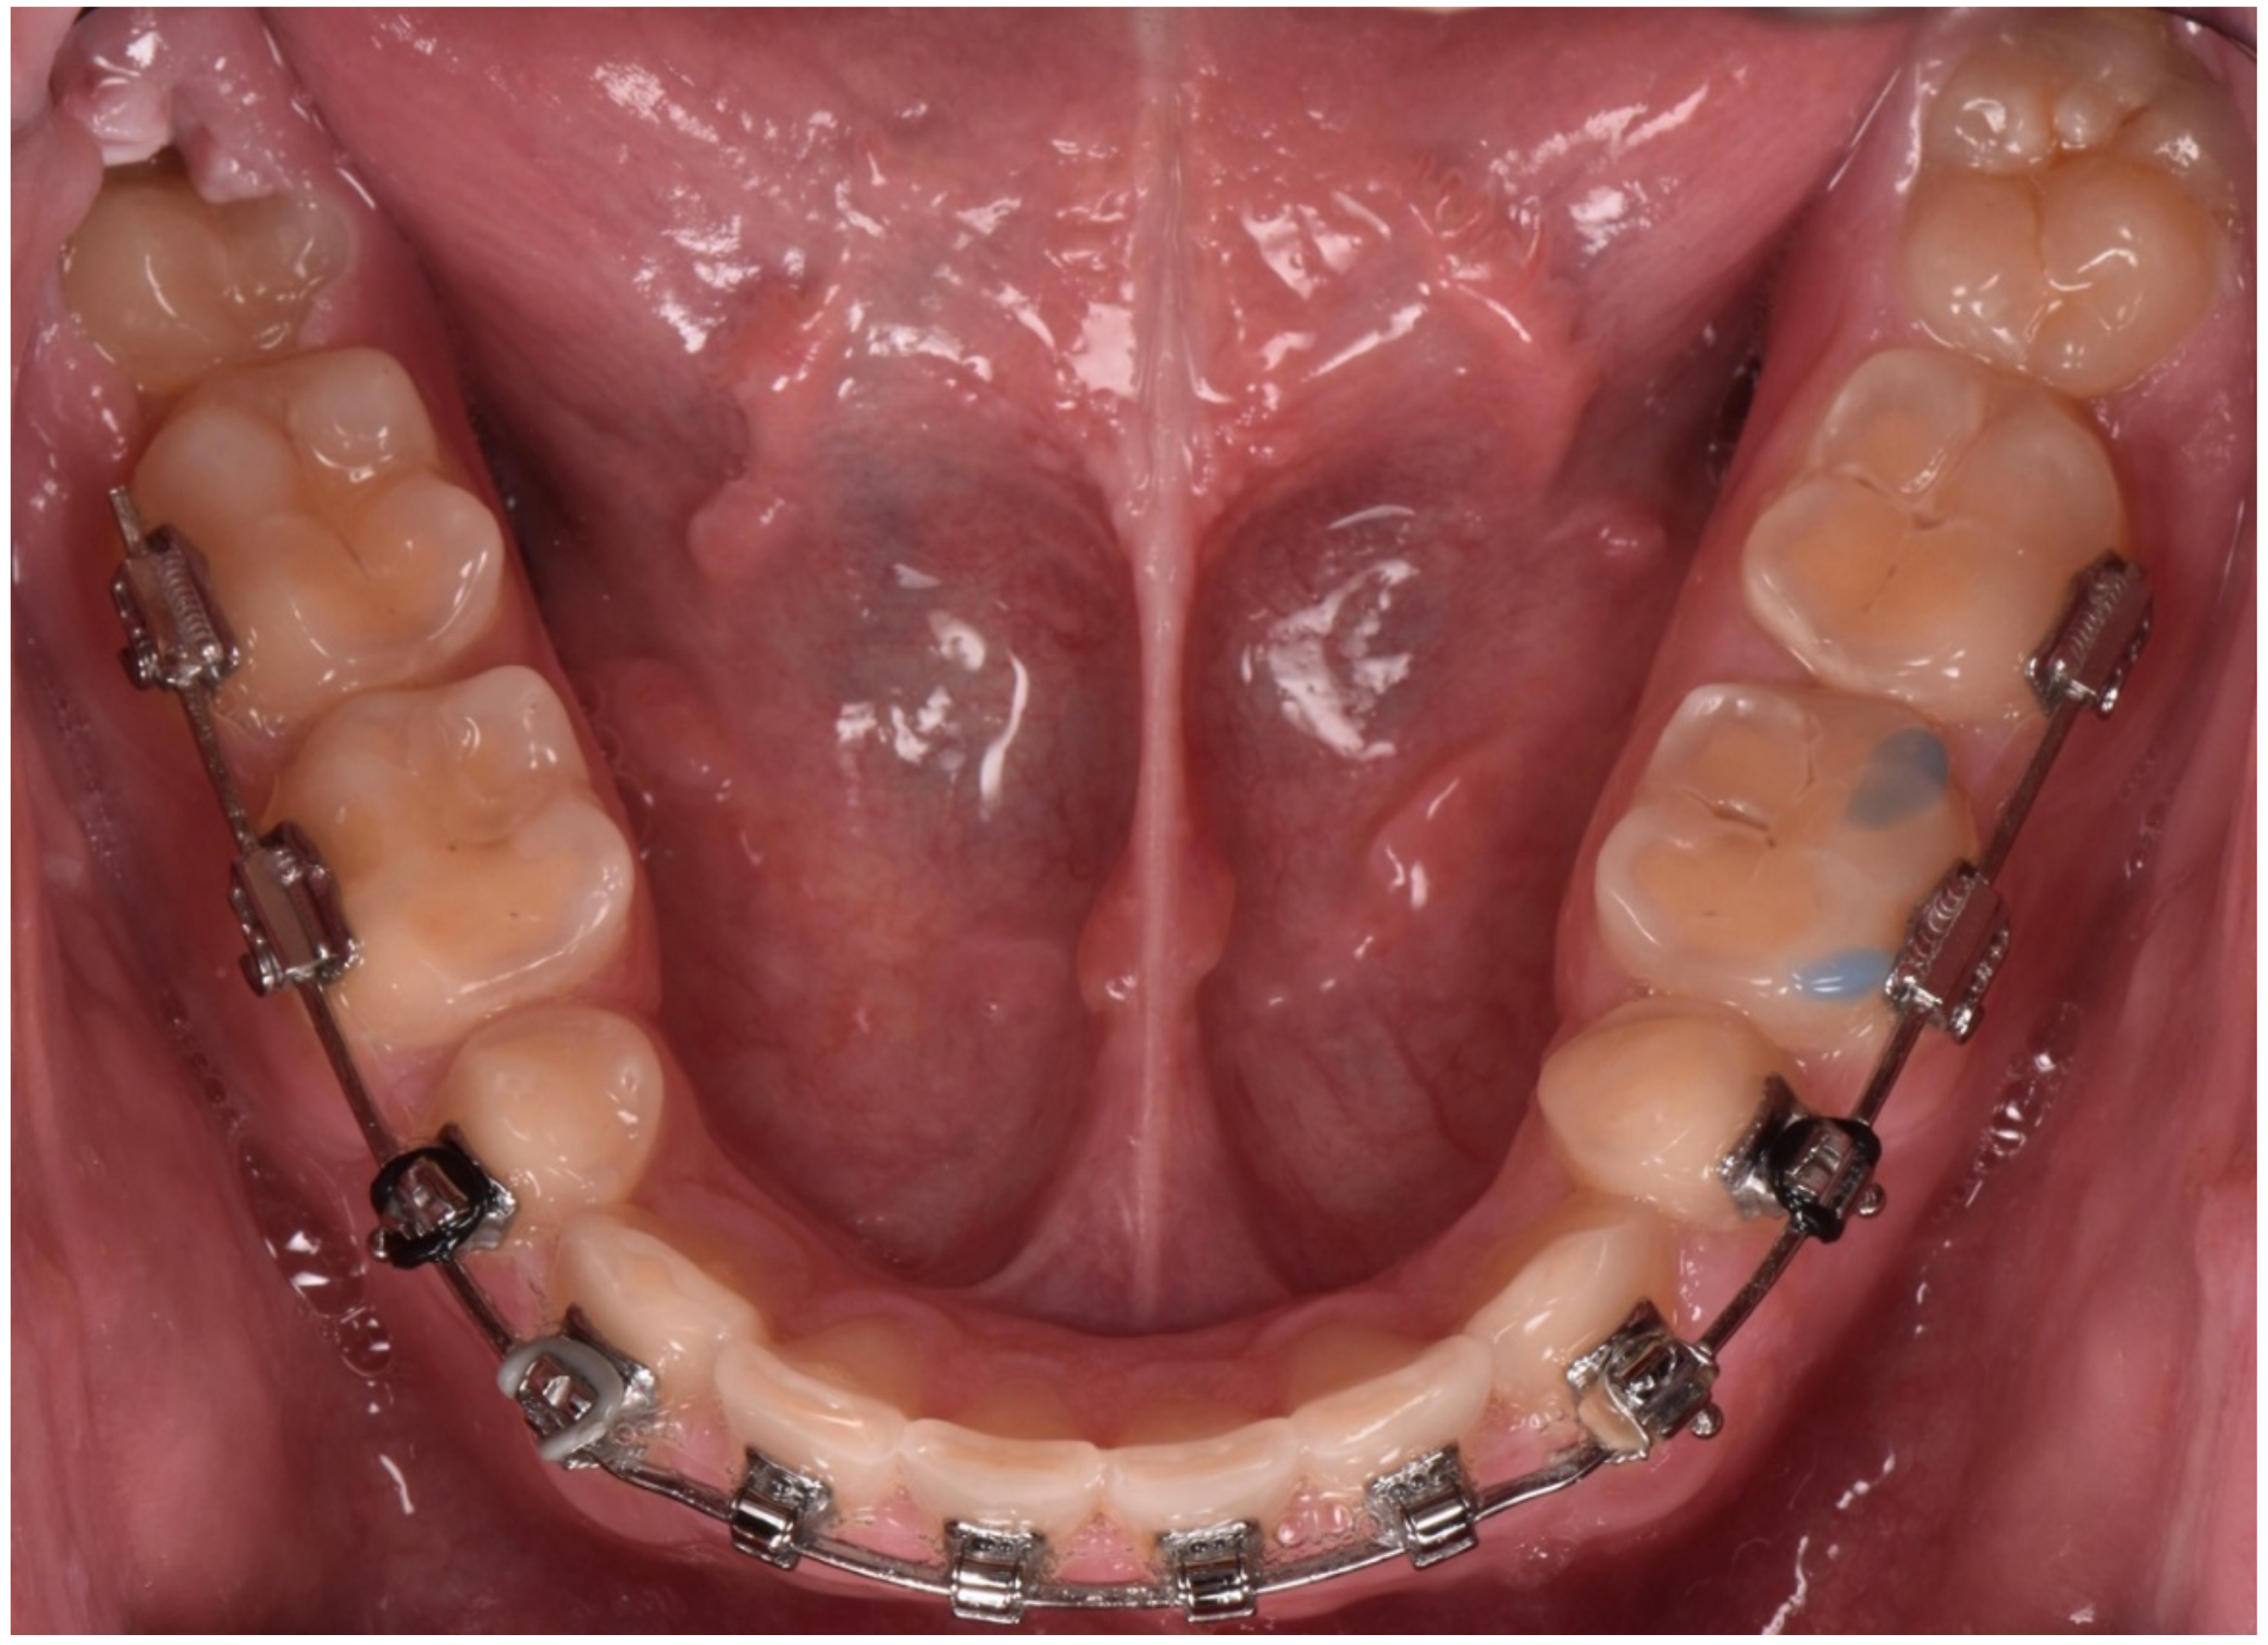

2. Clinical Report

2.1. Planning Phase

2.2. Restorative Phase